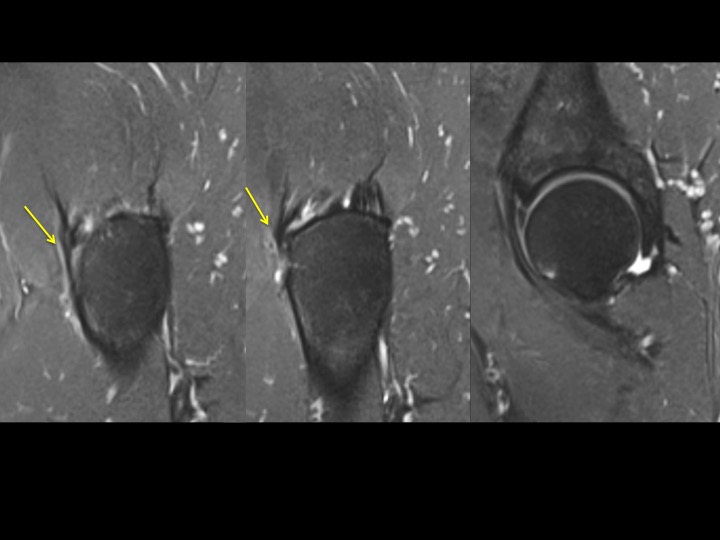

42M chronic pain with reported work injury 17 months ago

There is marked dark signal capsular thickening anteriorly and superiorly (white arrows). The reference, based on arthrography, refers to much thinner capsular measurements, and does not specify where measurements are made (these are mid superior and anterior). Is this chronic adhesive capsulitis? There is also insertional G Minimus tendinosis (yellow arrows) and degenerative tearing of the anterior labrum. The patient specified that pain is worst posteriorly. Last image from a different patient today with comparatively normal appearing capsule. Reference article.